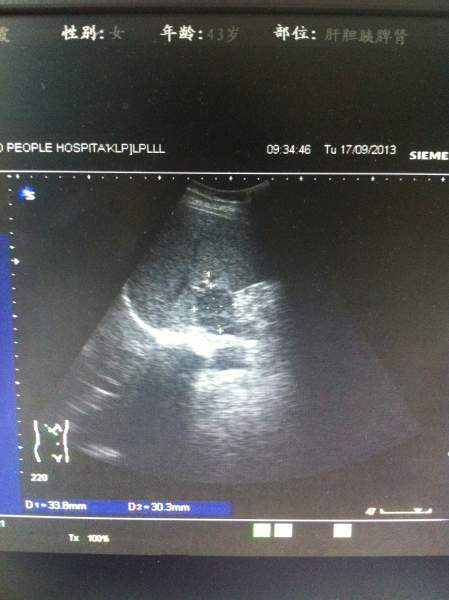

超声图像,各位大侠帮忙看下,肝上的这块是不是占位? 已有2人参与

患者今天前到我单位体检,两月前在另一单位体检过,结果正常,这次看肝上像有异常回声,让她再去上级单位复查,第二天患者去了,复查结果说是正常。 难道我们图像显示的是肝尾叶?回声可以这么低吗?看着还有边界的样子,难道是部分容积效应?真心很纠结,求指教,谢谢! IMG_1411.JPG IMG_1412.JPG IMG_1413.JPG IMG_1416.JPG |